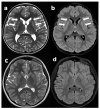

The "Spazio Huntington-A Place for Children" program was launched in 2019. The aim was to contact at risk kids within Huntington disease (HD) families, to provide counseling to their parents and to start a prospective follow-up of kids suspicious to manifest pediatric HD (PHD). We met 25 at risk kids in two years, four of whom with PHD and highly expanded (HE) mutations beyond 80 CAG repeats. We rated motor, neuropsychological and behavioral changes in all PHD kids by the Unified HD Rating Scale (UHDRS)-total motor score (TMS) and additional measures of (1) cognitive level (Leiter International Performance Scale), (2) adaptive functioning (Adaptive Behavior Assessment Systems), (3) receptive language (Peabody Picture Vocabulary Test) and (4) behavioral abnormalities (Child Behavior Check List and Children's Yale-Brown Obsessive Compulsive Scale). All PHD kids showed a severe progression of neurological and psychiatric manifestations including motor, cognitive and behavioral changes. The magnetic resonance imaging contributed to confirm the suspicious clinical observation by highlighting very initial striatum abnormalities in PHD. Spazio Huntington is a program to prospectively study PHD, the most atypical face of HD, and may represent the basis to recruit PHD patients in future clinical trials.